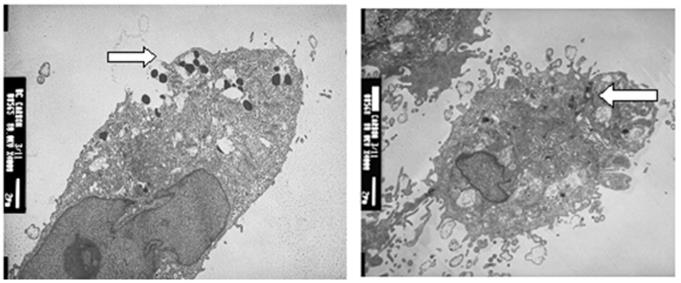

Effect of SWNTs-NefM1 conjugates on growth of tumorspheres

SWNT-NefM1 was internalized by cells. Transmission electron micrographic (TEM) images of MDA-MB-231 (positive for CXCR4 receptors) and MDA-MB-468 (negative for CXCR4 receptors) cells with internalized SWNT-Nef-M1, indicating entry of the complex into both cell types.